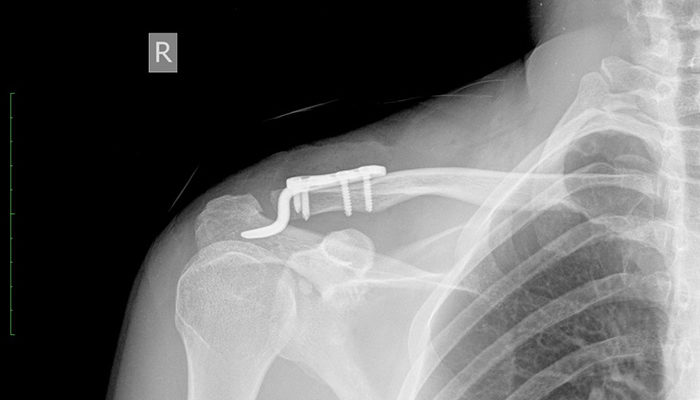

Распознать вывих достаточно просто на основании ярко выраженных внешних симптомов и собеседования с пациентом. Рентгенологическое обследование проводилось для уточнения диагноза и выявления повреждений кровеносных сосудов, нервных окончаний и близлежащих тканей.Если у врача возникают дополнительные вопросы и сомнения по поводу диагноза, рекомендуется компьютерная томография. Этот тест позволяет послойно осмотреть поврежденный участок.

Только после внимательного изучения изображений врач ставит окончательный диагноз и назначает соответствующее лечение.

Если консервативное лечение неэффективно и травма носит хронический характер, пациента направляют в больницу и оперируют вывихнутый конец ключицы. Во время него разорванные связки сшиваются, а части поврежденного сустава иммобилизуются различными способами.

Хирургическая операция

Фиксация кости спицами. Этот метод несколько устарел и менее эффективен. При его употреблении болезнь часто рецидивирует.

Наиболее распространены следующие оперативные методы лечения.

- Крепление саморезами. Этот метод более надежен, но снижает подвижность конечностей в период его использования. Рецидивы случаются гораздо реже.